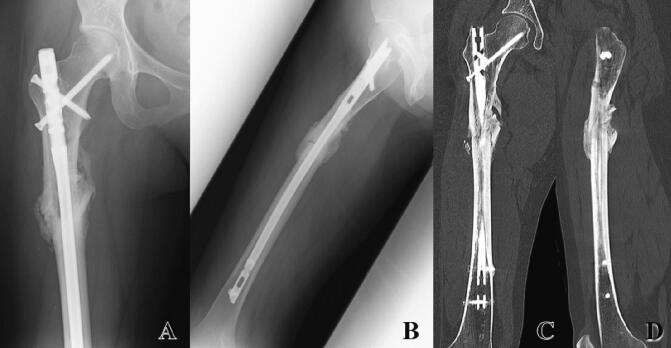

Atypical femoral fractures (AFFs) occur with minor trauma and are believed to be a potential complication of the prolonged use of antiresorptive agents, such as bisphosphonate and denosumab, for the treatment of bone metastasis. In comparison with typical femoral fractures, AFFs have a higher incidence of complications, including implant failure and delayed union or nonunion. This report describes the case of a 42-year-old woman who developed denosumab-associated AFF after denosumab therapy for bone metastasis from breast cancer. Surgical treatment with IMN was performed after open anatomical reduction. To reduce the risk of delayed union and nonunion, the autogenous bone graft obtained from the iliac crest was conducted. The radiograph taken 5 weeks after surgery showed callus formation. Full weight bearing was allowed 3 months after surgery. Six months postoperatively, radiographs and computed tomography images demonstrated bone union. Twelve months after surgery, the patient was able to walk easily without pain. For cancer patients with bone metastasis whose life expectancy may be limited, a decline in physical activity can be fatal. Consequently, it is crucial to avoid a decrease in activities of daily living brought about by delayed union or nonunion. In this regard, autogenous bone grafting is a viable and effective technique for the treatment of AFFs in patients with bone metastases.

非典型股骨骨折(AFFs)在轻微创伤后发生,被认为是长期使用抗吸收剂(如双膦酸盐和地诺单抗)治疗骨转移的潜在并发症。与典型股骨骨折相比,AFFs的并发症发生率更高,包括植入物失败和延迟愈合或不愈合。本报告描述了一名42岁女性在接受地诺单抗治疗乳腺癌骨转移后发生地诺单抗相关AFF的病例。在开放解剖复位后进行了髓内钉固定术。为降低延迟愈合和不愈合的风险,取自髂嵴的自体骨移植。术后5周拍摄的X线片显示有骨痂形成。术后3个月允许完全负重。术后6个月,X线片和计算机断层扫描图像显示骨愈合。术后12个月,患者能够轻松行走且无疼痛。对于预期寿命可能有限的骨转移癌患者,身体活动的减少可能是致命的。因此,避免因延迟愈合或不愈合导致的日常生活活动减少至关重要。在这方面,自体骨移植是治疗骨转移患者AFFs的一种可行且有效的技术。